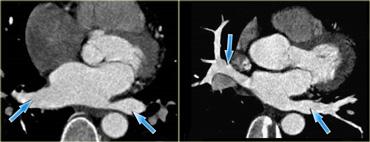

Tái tạo mặt cắt ngang (trái) và mặt cắt vành chếch (phải) của tim, mô tả nhĩ phải và các mạch máu chính dẫn vào: xoang vành (mũi tên xanh) và tĩnh mạch chủ trên và dưới. IVC=tĩnh mạch chủ dưới, A=trước, SVC=tĩnh mạch chủ trên

Tái tạo mặt cắt ngang (trái) và mặt cắt vành (phải) cho thấy mào tận cùng (mũi tên xanh) và vị trí của nó trong nhĩ phải

Trên các hình ảnh bên trái, nó hiện diện như một cấu trúc tuyến tính nhẵn (mũi tên xanh).

Tuy nhiên, điều này không phải lúc nào cũng như vậy; đôi khi nó có thể giả dạng một khối.

Tái tạo mặt cắt ngang (trái) và mặt cắt vành chếch (phải) cho thấy xoang vành khi đi vào nhĩ phải (mũi tên xanh). A=trước, P=sau